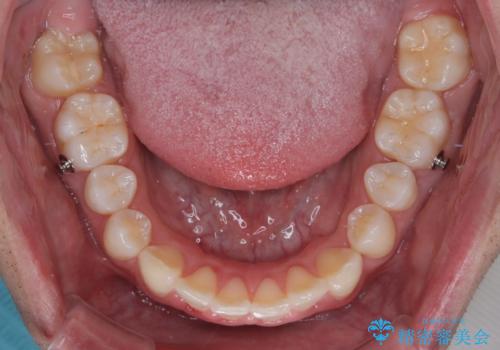

インビザラインによる矯正治療をご希望でしたが、上顎歯列の前方位と鋏状咬合を確実に改善することを目的として、補助装置を併用することとしました。

補助装置を併用せずに治療を終える可能性はありましたが、確実に結果を得るために補助装置を活用しました。

イメージしたとおりの仕上がりとなりました。